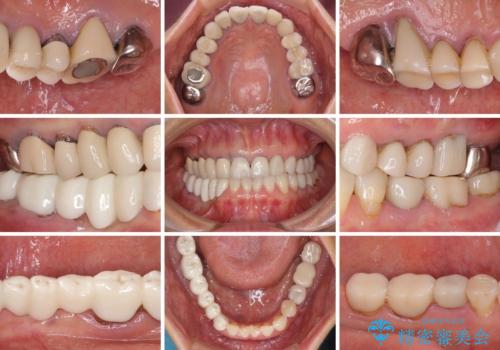

- 以前治療した歯が欠けたり、痛みを感じたりしているとのことで来院された患者様です。

アメリカ国内を転々としながら治療を行ったため治療跡がモザイク様で、クラウンが壊れていたり、抜歯が必要であったりしていました。

上下左右すべての奥歯に処置が必要であり、同時に行うと食事が取りにくくなってしまったり、手前の歯に負担がかかって初診時よりも状況が悪化したりする可能性があるため、片方ずつ処置を進めて行くこととしました。

下顎右側は骨造成を併用してインプラント治療を行い、その他の奥歯もインプラントや歯周外科処置を併用して補綴治療を進め、最後に前歯部の欠けてしまったセラミッククラウンを作り替えることとしました。

海外を拠点に仕事をされているため、日本国内への入国規制の時期が重なってしまい、予定していたよりも1年ほど長い治療期間がかかってしまいました。